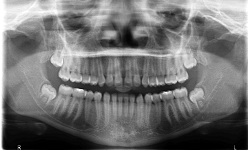

Records taking, Diagnosis, Treatment Plan, Classification and Fee.

In this phase Cephalometric X-Rays(above), Panoramic X-Rays(below), Orthodontic Photos(Interoral and Extraoral) and Impression(Molds) are made and taken for study purposes.